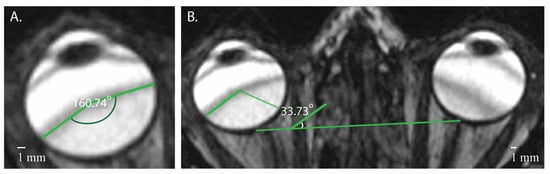

3.2. Signal Areas in the Eye

| Right eye | * 1.47 (1.41) | * 142.60 (13.76) | 58.01 (24.66) |

| Left eye | * 1.27 (0.64) | * 148.10 (14.21) | 54.47 (24.46) |